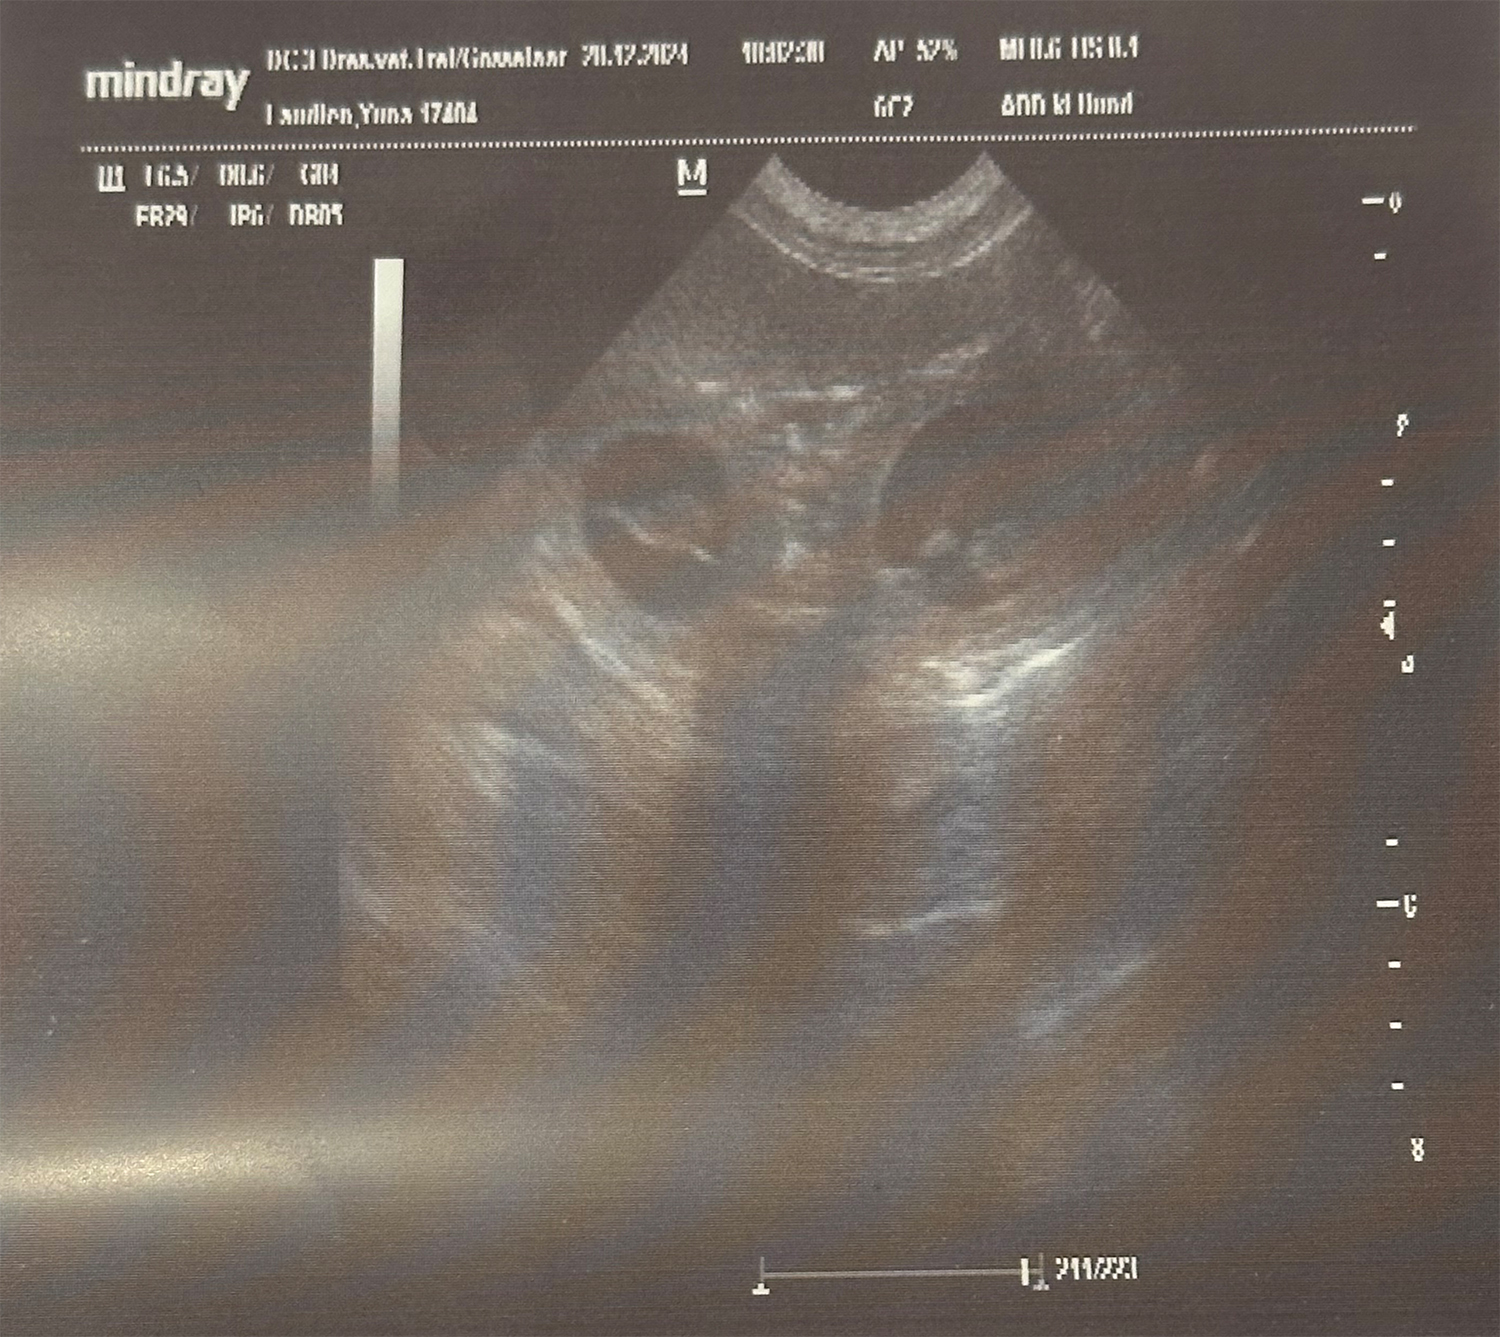

Heute war also der Tag der Tage. Der Tag an dem man Gewissheit bekommt, ob die Hündin aufgenommen hat oder nicht.

Auch wenn in den letzten Tagen einiges für eine Trächtigkeit gesprochen hat, so wollten wir es gerne

von unserer Tierärztin Dr. Insa Gosselaar absegnen lassen.

Beim Ultraschall wurden auf Anhieb einige Fruchtanlagen gesichtet. Die genaue Anzahl wollte ich aber nicht wissen.... ein bisschen Spannung soll uns und den Welpeninteressenten schon noch in den kommenden Wochen erhalten bleiben.  |

Wir freuen uns einfach riesig darüber, dass bald kleine M-Racker den Bagalutenhof besetzen werden.

Bis dato werden wir Yuna fit halten und gut auf unser Essen aufpassen. |